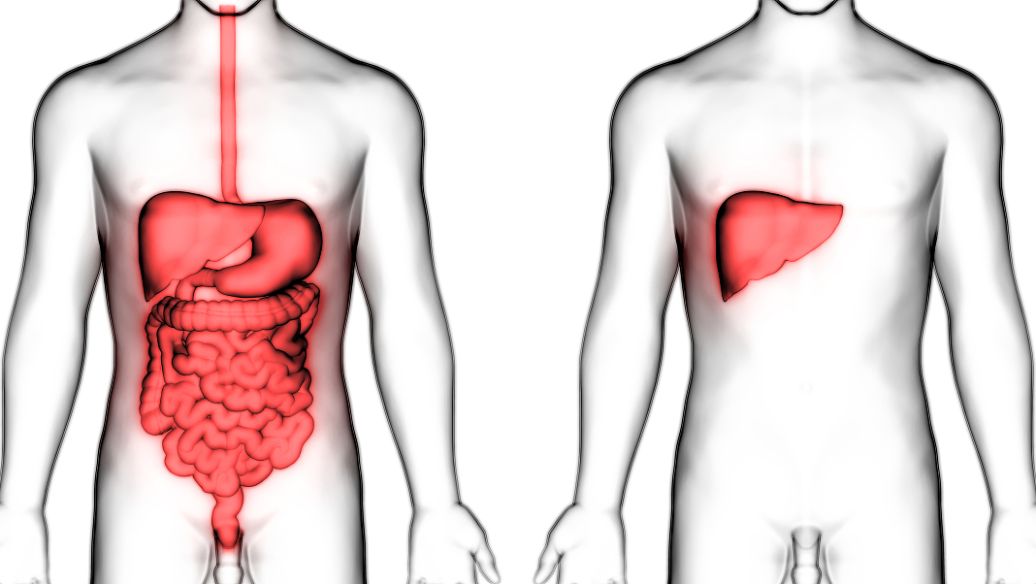

同房过后小腹痛最常见的原因有两点:压力刺激过大、女性自身妇科病导致同房后小腹痛。

1.压力刺激过大:女性的尿道、阴道和膀胱是互相靠着的,子宫离阴道比较近,所以在进行性生活的时候,外加的压力和性欲望的亢奋就容易出现收缩和痉挛,小腹疼痛也会经常发生。进行性生活时,男性用力过猛会造成阴道以及内部结构受到严重挤压导致女性小腹疼痛。

2.女性自身妇科病导致同房后小腹痛:部分女性在日常生活中不注意卫生,容易引起妇科疾病,当子宫和宫颈出现炎症的时候,性生活也没有进行全面的保护,再受到男性生殖器的挤压下会导致腹痛,炎症严重者的女性事后还会出现少量出血。在进行性生活之前,一定要保持生殖器卫生。如果性生殖器官不清洁,就会在性生活时把很多脏东西带入到女性阴道里,从而导致感染。